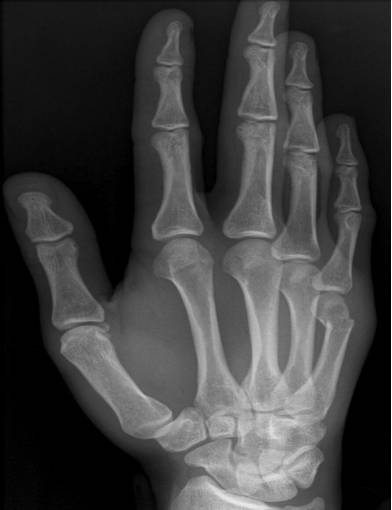

Bennett骨折

第一掌骨基底部关节内骨折伴脱位。

Rolando骨折

纵向暴力导致第一掌骨基底部劈裂骨折。属于关节内骨折。